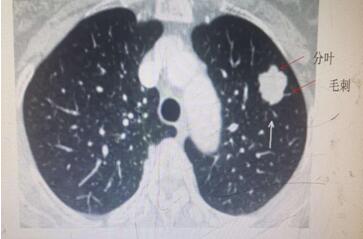

肺內結節,不容忽視,但也不必驚慌。肺部小結節并非一定就是肺癌,惡性腫瘤遠少于良性病變。一般根據結節大小、形態并結合你的年齡與吸煙狀況來分析。通常以下情況肺癌的可能性大:年齡在55歲以上;有慢性肺部疾病史和家族史的患者;肺部小結節直徑>1厘米;邊緣有毛刺和分葉;內部密度不均勻表現為實性結節或者混雜性結節。需要注意的是,有吸煙史的人,是肺癌的高危人群,年數乘以每天吸煙的支數>400支/年的吸煙患者患肺癌的幾率會明顯增高。